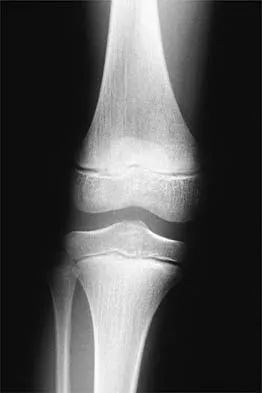

Figures 12a and 12b show the radiographs of a 50-year-old patient who reports acute knee pain after sustaining a twisting injury while playing tennis. Examination is unremarkable. The next most appropriate step in management should consist of

Explanation

The radiographs show localized diffuse cortical thickening that is characteristic of melorheostosis. The condition may be monostotic or it may involve many bones in one extremity (monomelic) in the distribution of a sclerotome. Bone scans will show increased uptake at the site or sites of skeletal involvement. Long tubular bones are most commonly involved. Melorheostosis is usually asymptomatic and requires no treatment. On rare occasions, there may be associated soft-tissue contractures. Dorfman H, Czerniak B: Bone Tumors. St Louis, MO, Mosby Inc, 1998, pp 1105-1107. Campbell CJ, Papademetriou T, Bonfiglio M: Melorheostosis: A report of the clinical, roentgenographic, and pathological findings in fourteen cases. J Bone Joint Surg Am 1968;50:1281-1304.